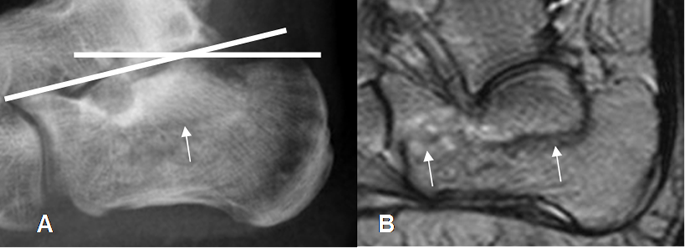

Fig 46 B. Fractura del calcáneo.

A: Rx lateral y B: RM sagital en T2. Fractura impactada, con disminución del ángulo de bohler.